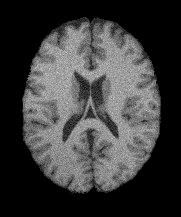

Magnetic Resonance Imaging (MRI) is a critical and widely used medical modality due to its noninvasive nature and ability to produce high-quality images of human organs and tissues. Segmentation in MRI refers to the process of dividing the acquired image data into specific tissues or regions of interest (ROIs). In the context of brain slice MRI data, this often involves distinguishing between cerebrospinal fluid (CSF), gray matter (GM), and white matter (WM), in 2D image slices as depicted in Fig. 1. Research topics on brain anatomy and functionality (e.g., Alzheimer’s disease, tumor detection, neurodegenerative processes, etc.) demand reliable segmentation tools since their outcomes directly impact the subsequent analysis of the brain slice MRI. Therefore, the development of any accurate MRI segmentation framework has to deal with the following issues:

(1) where can be interpreted as a smoother version of . With a little abuse of notation, we indicate the equation (1) as a cartoon-texture (CT) decomposition (even though we do not aim to compute a proper CT decomposition), where is the ‘cartoon’ depicting the structural component, and the ‘texture’ part including oscillatory components, like texture and noise, as shown in Figure 1.

Figure 3 illustrates the workflow of the algorithm SegMIC2T using the slice060 with low (top row) and moderate (bottom row) levels of the combined artifacts. The noise estimation step splits the original MRI slice into a cartoon image (second column) and a texture image (third column) (1). The correction step, coinciding with the application of the proposed multiaffine ADMM method, produces a denoised and debiased version of the original slice, whose th pixel corresponds to (fourth column). In the last step, the segmentation of the original slice is produced by clustering the pixels in the corrected image (fifth column).